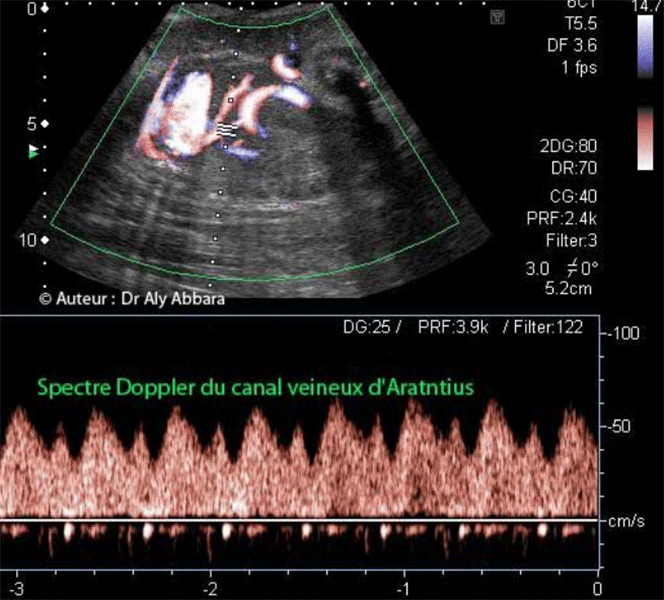

Image échographique comparant le spectre du Doppler du canal veineux d'Arantius au spectre

du Doppler des veines hépatiques (droite et gauche) afférentes à la portion terminale de la

veine cave inférieure ; puis la veine ombilicale, juste avant sa connexion au canal veineux.

(Age fœtal = 31 SA) |

- Le spectre du Doppler du canal veineux (canal d'Arantius ou ductus venosus) est composé de deux pics (S et D) et d'une incisure (a), ces composants correspondent dans le cycle cardiaque aux phases suivantes :

- Pic (S) = systole ventriculaire droite

(contemporaine du remplissage de l'oreillette droite)

- Pic (D) = diastole ventriculaire droite

(ouverture de la valve tricuspide)

- Notch (incisure) a = contraction de l'oreillette droite en

télédiastole (atrial systole).

- Ce spectre est aussi le reflet des pressions veineuses centrales fœtales qui dominent dans l'oreillette droite et ses veines afférentes.

- Sur le spectre du Doppler du canal veineux, la distance séparant le notch (a) de la ligne de base (zéro) correspond au flux sanguin veineux persistant au cours de la systole auriculaire droite.

- Normalement ce flux est toujours positif, et il est considéré comme pathologique quand il est nul ou négatif, c'est-à-dire si le fond du notch (a) revient au zéro ou quand il devient négatif " (ou inversé)" a(reverse flow).

- L'insuffisance vasculaire utéro-placentaire et l'hypoxie fœtale secondaire peuvent se traduisent sur le Doppler du canal veineux par un notch (a) à zéro ou négatif (témoigne d'une insuffisance myocardique).

- Au cours du premier trimestre de la grossesse, entre 11 et 13 SA, le notch (a) est normalement positif ou nul. Un notch négatif (inversé) est retrouvé chez 65 % des fœtus trisomiques 21 ; 55 % des fœtus trisomiques 18 ; 55 % des fœtus trisomiques 13 et seulement 3 % des fœtus euploïdes.

Un notch (a) pathologique au premier trimestre de la grossesse peut aussi témoigner de la présence d'une anomalie cardiaque majeure.